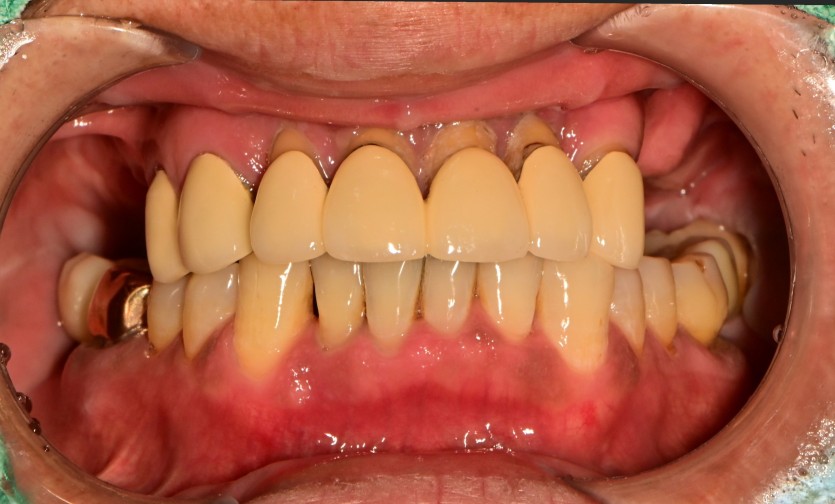

만 65세 상악 전체 임플란트 증례 (하악 전치부)

상악 전체 임플란트 증례입니다.(하악 전치부)

12개의 임플란트로 완성하였습니다.